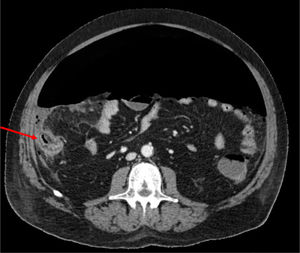

Se trata de un varón de 66 años, con síndrome metabólico como único antecedente de interés y sin tratamiento habitual; en el contexto de un cuadro de insuficiencia respiratoria aguda secundaria a COVID 19, presentó dolor abdominal con defensa y aumento de leucocitosis y de PCR asociado. Tras la realización de una TC abdominopélvica se identifica abundante neumoperitoneo secundario a perforación de colon derecho. Se realizó una colectomía derecha, no observando signos de isquemia, ni divertículos en la pieza extraída.

Anteriormente había recibido tratamiento con metilprednisolona 100mg/día (durante 5 días), tocilizumab (dosis única de 600mg, correspondiente a 8mg/kg) y 15 días previos a la intervención, azitromicina, hidroxicloroquina y lopinavir/ritonavir. La biopsia revela un área de necrosis con ulceración de la mucosa de 12mm en cara anterior del ciego, sin signos de malignidad ni otras áreas de isquemia.